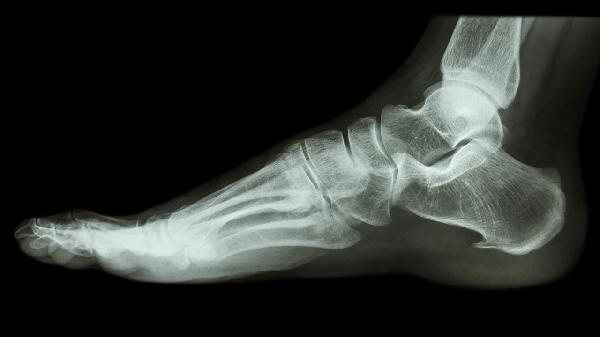

脚拇趾骨外凸疼痛可通过穿戴矫形器、物理治疗、药物治疗、手术治疗等方式缓解。该症状通常由穿鞋不当、足部畸形、关节炎、痛风等原因引起。

1、穿戴矫形器

选择宽松舒适的鞋子,避免高跟鞋或尖头鞋,可使用拇外翻矫形器或分趾垫减轻局部压力。

2、物理治疗

通过冰敷缓解急性疼痛,热敷促进血液循环,配合足底肌肉锻炼帮助改善足弓支撑力。

3、药物治疗

可能与骨关节炎、滑囊炎等因素有关,通常表现为红肿热痛。可遵医嘱使用布洛芬缓释胶囊、塞来昔布胶囊、双氯芬酸钠凝胶等药物。

4、手术治疗

可能与严重拇外翻畸形有关,通常伴随行走困难。需进行截骨矫形术或关节融合术等手术矫正骨骼结构。

日常避免长时间站立行走,控制体重减轻足部负荷,疼痛持续加重建议及时就医评估。